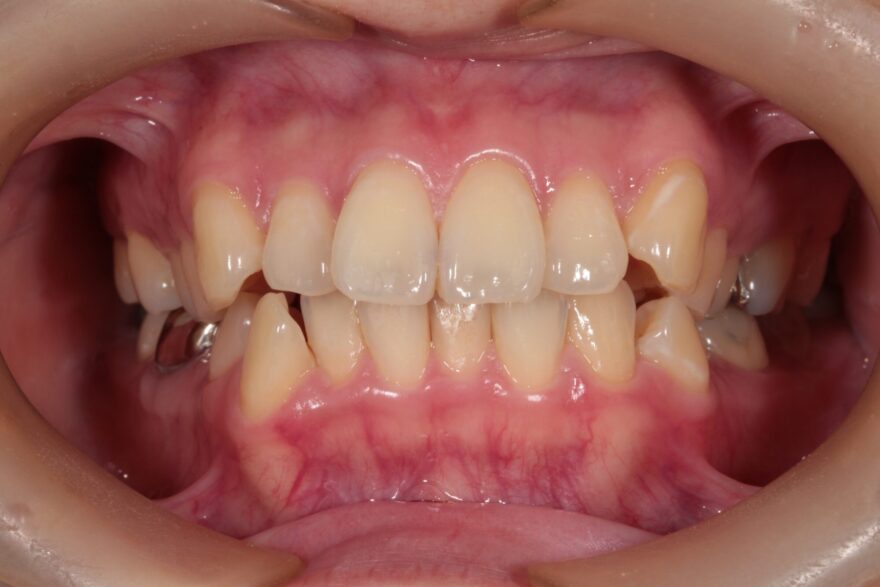

昔から前歯の重なりや全体的な歯並びの悪さが気になっていて、口元にコンプレックスがありました。

ガタガタに重なっている部分や、過去の治療で銀歯も入っています。